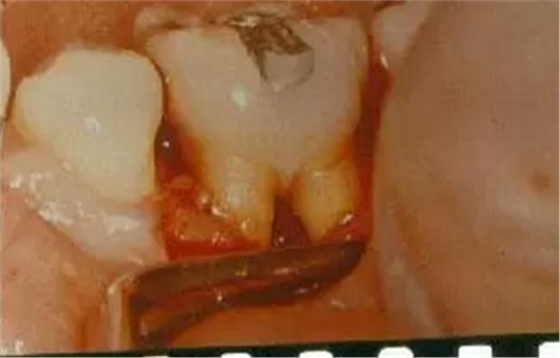

8、根分叉病變的檢查

根分叉病變是指牙周炎發(fā)展到較重的程度后,病變累及多根牙的根分叉區(qū),它可發(fā)生于任何類型的牙周炎。下頜第一磨牙患病率最高,上頜雙尖牙患病率最低。發(fā)生率隨年齡增大而上升。

操作方法:

用普通的彎探針或?qū)iT設(shè)計的Nabers探針探查多根牙的分叉區(qū)。檢查上頜磨牙時,先探查頰側(cè)中央處的根分叉區(qū),再從腭側(cè)分別探查近中和遠中的根分叉區(qū),但有的會有變異,需從頰側(cè)探入;檢查下頜磨牙時,從頰側(cè)和舌側(cè)中央處分別探查根分叉區(qū)。探查的內(nèi)容應(yīng)包括:探針能否水平方向探入分叉區(qū),水平探入的深度,分叉的大小,有無釉質(zhì)突起,根柱的長度,根分叉區(qū)是否有牙齦覆蓋,注意檢查根分叉區(qū)是否暴露。

牙周袋和骨吸收波及根分叉區(qū),可從臨床上探查到。主要根據(jù)探診和X線片來判斷病變的程度。Glickman將其分為四度,此分類法有利于指導(dǎo)治療和判斷預(yù)后。